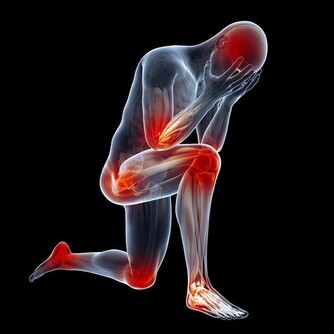

如果經常出現以下症狀,則說明身體內的毒素積累過多,許多疾病產生的根源也是由於大量毒素的堆積

1經常疲倦、精力差、感冒或身體過熱,易出汗、手足潮濕。倘若人體內的毒素積累到一定的程度,就會增加體內各個器官和系統的負擔,從而出現疲勞等現象

2皮膚乾燥或油膩,易起紅疹、色斑、小疙瘩、易過敏,皮膚是排除體內毒素和垃圾的重要途徑,這些症狀是體內有毒素的信號

3口臭、屁臭、打嗝、脹氣、腹脹、便秘,這些問題的產生主要是腸道廢物積累過多的緣故

4頭腦混濁、記憶力下降、易怒,身體內的毒素積累過多,器官壓力過大或者體內循環不暢都會導致供血供氧不足,影響大腦正常工作,引發情緒和精神問題

5尿頻、尿少、尿刺痛、四肢腫脹,這說明某些致病因素或毒素過多,影響了腎臟的正常功能